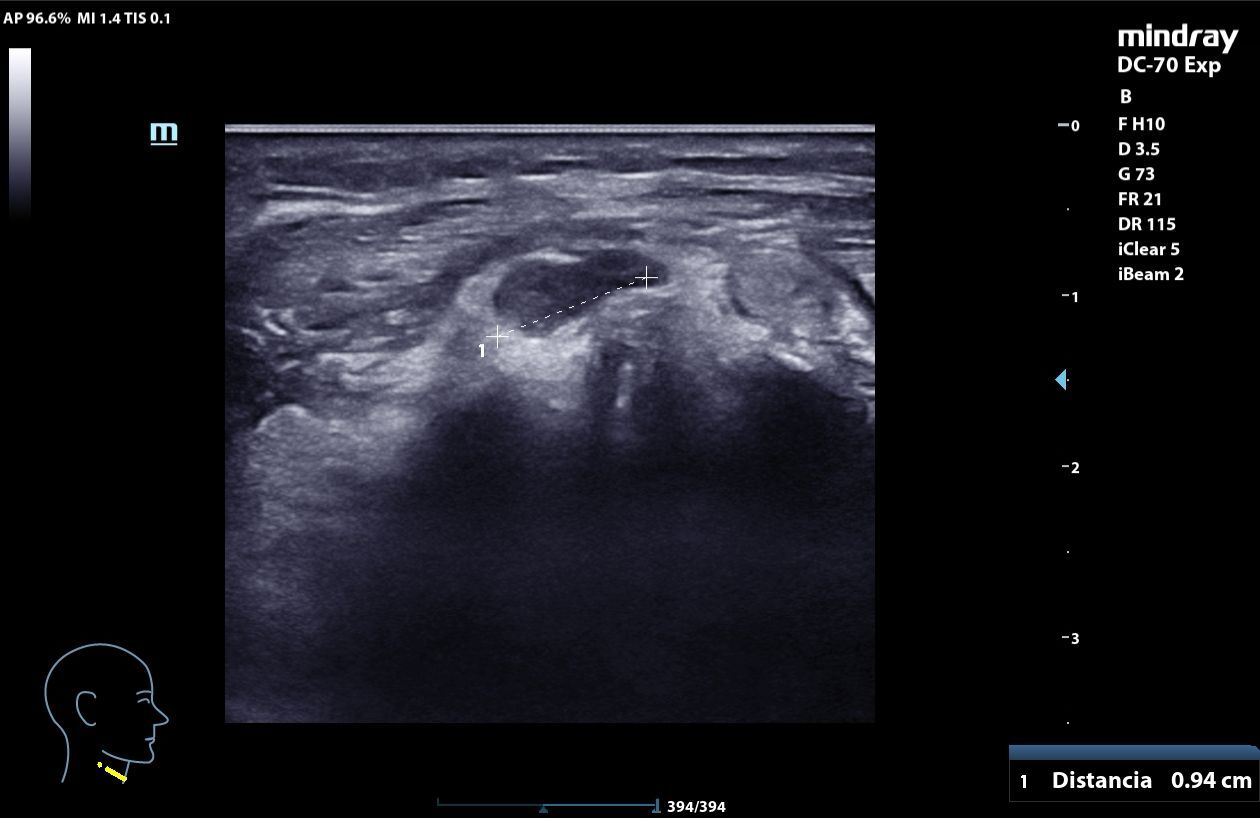

A nivel medial del cuello, por encima del cartílago cricoideo, masa heterogénea, mal delimitada, con calcificaciones internas que generan sombra acústica posterior, elementos hiperecogénicos y algunas zonas anecoicas con refuerzo posterior, con captación en Doppler. La lesión mide 3,06 x 1,48 x 2,78 cm y se mueve con la deglución. En relación con quiste tirogloso complicado o proceso neoformativo.